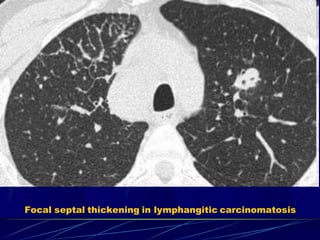

Interlobular septal th. – lymphangitic carcinomatosis

 tumor filling of pulmonary vessels and lymphatics

 direct tumor infiltration of the interstitium

 vascular and lymphatic distension distally to tumor

emboli or obstruction

 breast ca.

 lung ca.

 stomach ca.

 pancreas ca.

Secondary to:

 prostate ca.

 adenoca. of

unknown origin

 smooth or nodular septal thickening

 smooth or nodular thickening of peribronchovascular

interstitium and fissures

 thickening of the intralobular axial interstitium

 focal or asymmetric distribution

In the reticular pattern there are too many lines, either as

a result of thickening of the interlobular septa or as a

result of fibrosis as in honeycombing.

Focal septal thickening in lymphangitic carcinomatosis